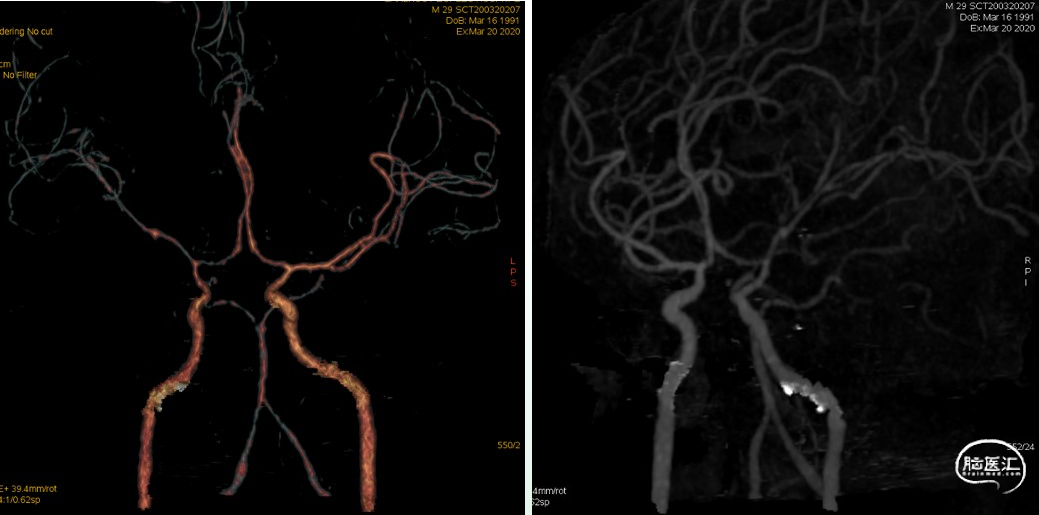

半年后颅骨修补前影像

颅骨修补后影像、随访

颅骨修补后1月预后情况:

神志清楚,精神状态正常,言语对答流利,定时定向力正常,四肢活动自如